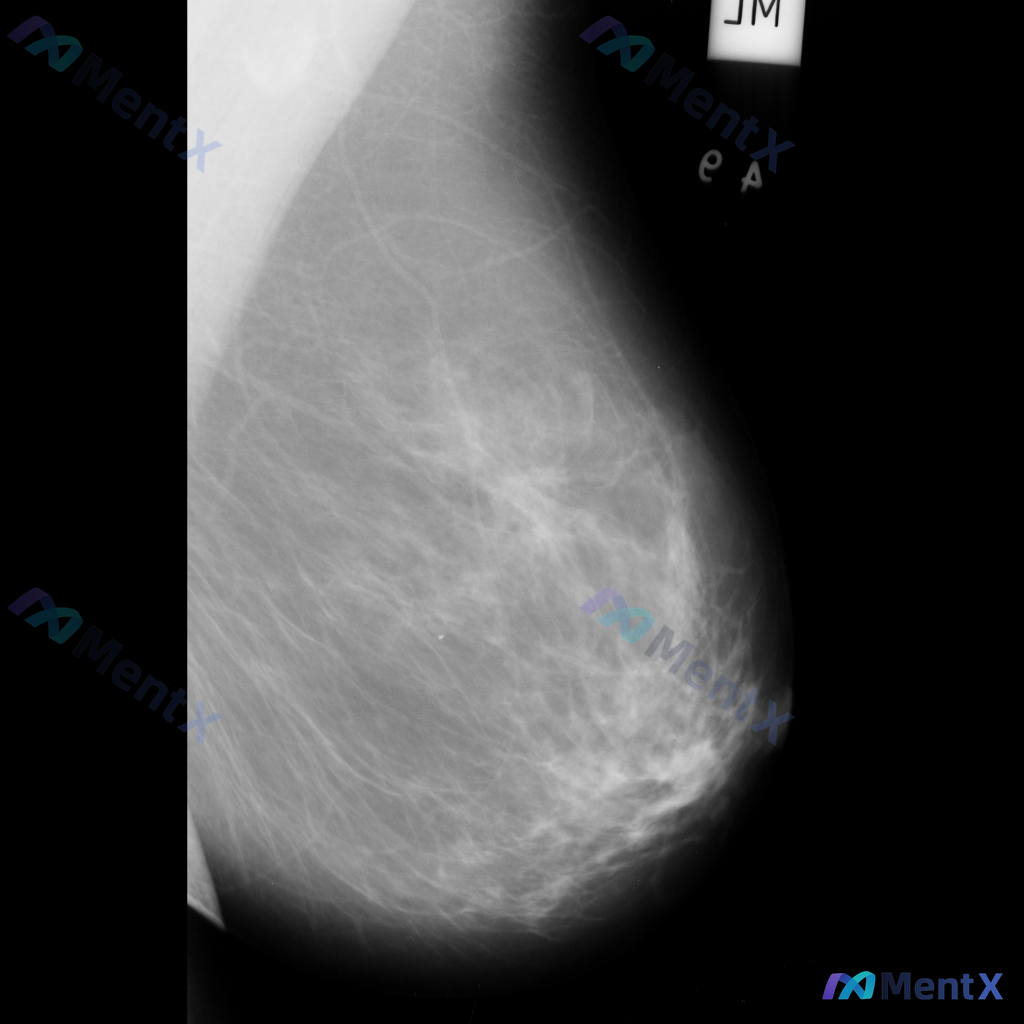

这张乳腺钼靶影像的异常表现,最适合用什么术语描述?

整理到一张乳腺钼靶影像资料,大家一起讨论下。 影像表现大概是这样: - 异常区域位于乳腺下象限偏外侧 - 可见一局限性致密影,形态大致呈卵圆形或不规则形 - 边缘部分清晰,局部可能模糊或有细微毛刺样改变 - 致密影密度高于周围脂肪组织,与纤维腺体组织密度相似或略高 - 周围乳腺小梁结构似有轻微的牵拉...

整理到一张乳腺钼靶影像的读片讨论资料: 影像显示右乳腺局部区域存在一不规则高密度肿块,伴有毛刺状边缘及局灶性结构扭曲。 想先跟大家讨论一下:单看这组特征,你首先会往哪个方向考虑?后续又会建议如何处理?

整理到一张乳腺钼靶影像资料,可见一处明确的异常表现: - 局部有形态不规则的占位性病灶,密度高于周围正常腺体组织 - 病灶边缘有细小的放射状结构向周围延伸 - 病灶周围的乳腺腺体和纤维组织结构排列紊乱 另外,该病例的乳腺组织整体密度较高(不均匀致密型)。 想和大家讨论:对于这张影像的异常表现,用哪些...